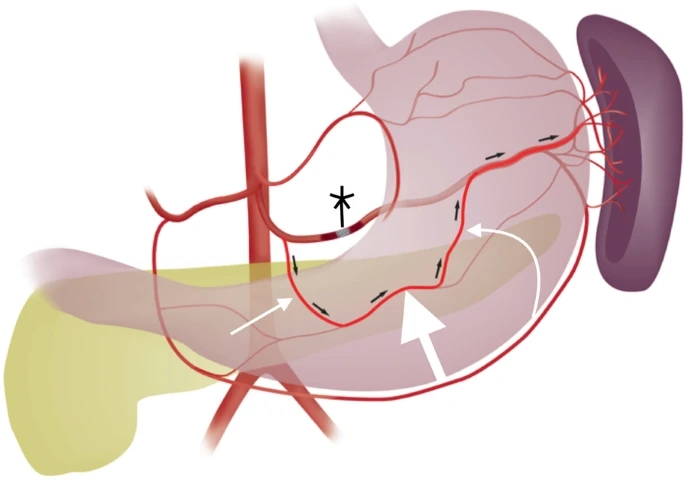

弹簧栓子的位置:胰大动脉和胰背动脉之间

|

白色细箭头:胰背动脉

白色粗箭头:胰横动脉

短黑箭头:血液流动方向

※:弹簧栓子 |